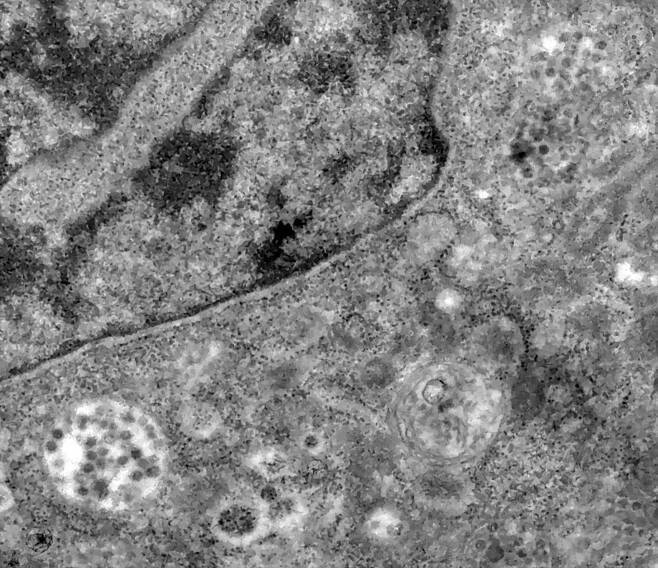

코로나19가 폐뿐 아니라 여러 장기를 손상시킨다는 사실이 부검으로 확인됐다. 아래 검은 점이 코로나19 바이러스. [이미지 출처: 브라질 국영 연구기관 ⓒ피오크루즈 재단]

왼쪽 하단에 세포 안으로 침입한 코로나19 바이러스 모습(축구공 모양). [이미지 출처: 브라질 국영 연구기관 ⓒ피오크루즈 재단]